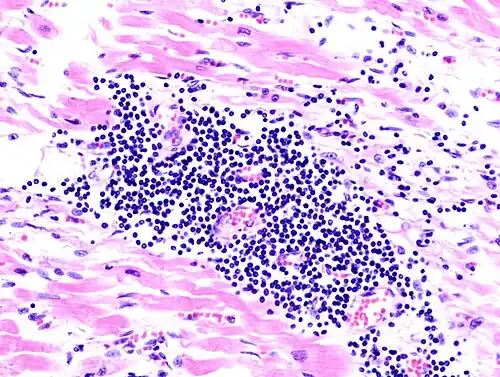

A microscope image of myocarditis at autopsy in a person with acute onset of heart failure. The black dots are primarily lymphocytes infiltrating the myocardium. | |

Most forms of myocarditis involve the infiltration of heart tissues by one or two types of pro-inflammatory blood cells, lymphocytes and macrophages plus two respective descendants of these cells, NK cells and macrophages. Eosinophilic myocarditis is a subtype of myocarditis in which cardiac tissue is infiltrated by another type of pro-inflammatory blood cell, the eosinophil. Eosinophilic myocarditis is further distinguished from non-eosinophilic myocarditis by having a different set of causes and recommended treatments.[36][20]

The gold standard is the biopsy of the myocardium, in general done in the setting of angiography. A small tissue sample of the endocardium and myocardium is taken and investigated. The cause of the myocarditis can be only identified by a biopsy. Endomyocardial biopsy samples are assessed for histopathology (how the tissue looks like under the microscope): myocardial interstitium may show abundant edema and inflammatory infiltrate, rich in lymphocytes and macrophages. Focal destruction of myocytes explains the myocardial pump failure.[12] In addition samples may be assessed with immunohistochemistry to determine which types of immune cells are involved in the reaction and how they are distributed. Furthermore, PCR and/or RT-PCR may be performed to identify particular viruses. Finally, further diagnostic methods like microRNA assays and gene-expression profile may be performed.